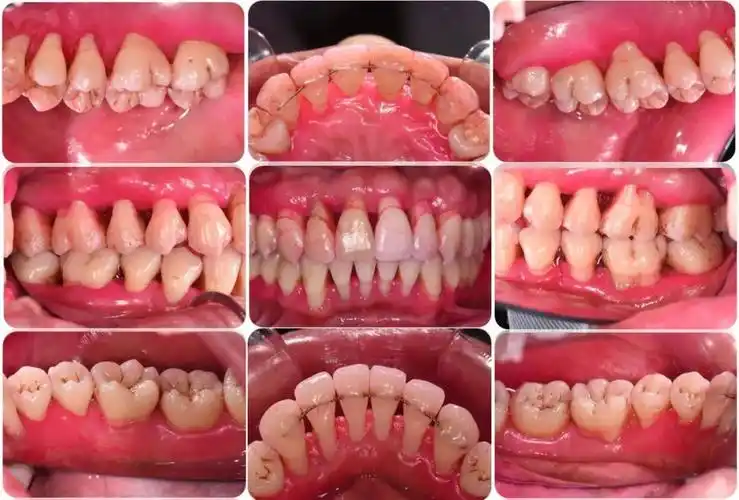

1例重度牙周炎的治疗